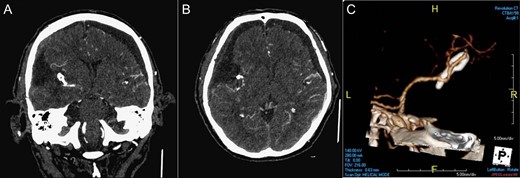

The patient recovered well after surgery and can achieve independent life. His early post-operative CTA of brain (Fig. 3) showed the complete removal of the tumor and the complete surgical clipping of the aneurysm without residual lesions. Post-operative adjuvant radiotherapy was arranged since intracranial solitary fibrous tumor/hemangiopericytoma grade 2 is locally aggressive.

Post-operative imaging. CTA of brain coronal view (A), axial view (B), 3D reconstruction (C) showing the complete removal of the tumor and the complete surgical clipping of the aneurysm without residual lesions.